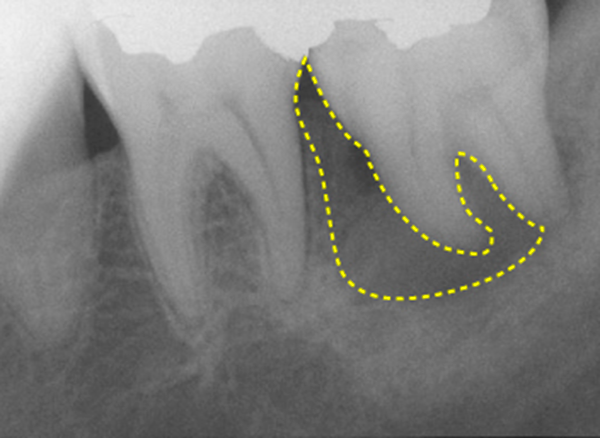

Bacteria that have reached the pulp will travel through the root canal, the cavity where the pulp used to be, to the the root apex, and finally proliferate in the bone that supports the tooth (Fig. 8).

This is called a "periapical lesion" (Fig. 9), and when this occurs, the tooth begins to move easily.

- Teeth with severely resorbed or fractured tooth-supporting bone(approximately 2/3 resorbed). (Figures 13 and 14)

- Teeth with severely resorbed roots (approximately 1/3 resorbed).